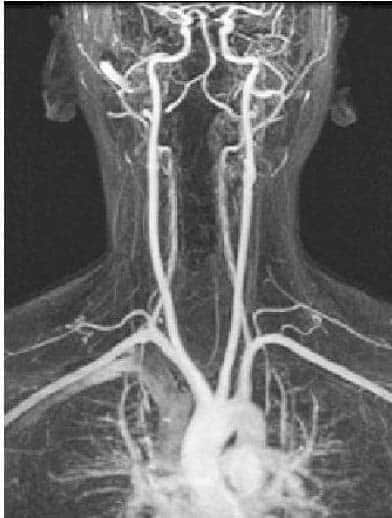

Fig 1.0 - Arteriogram of the arterial supply to the CNS.

Arteriogram of the arterial supply to the CNS.